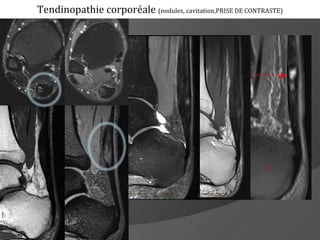

Tendinopathie corporéale (nodules, cavitation,PRISE DE CONTRASTE)